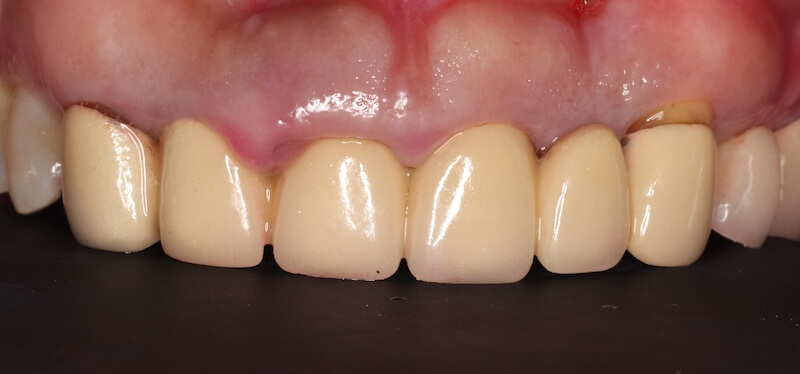

在這個相對健康的牙周環境狀態下,我們利用DSD數位微笑設計,全數位化的口內掃描並製作出第二組臨時假牙,透過這組假牙置放在口內和她討論未來正式假牙的外型與顏色。

經過第二組臨時假牙的配戴,我的建議會是有兩處牙周相關的問題可以做改正:

- 原本兩顆正中門牙的長度並不一致,我們可以利用水雷射進行牙冠增長術。以不開刀的方式雕塑牙齦和內部的齒槽骨,也不需要縫合。讓兩顆正中門牙盡量達到視覺上長度一致。